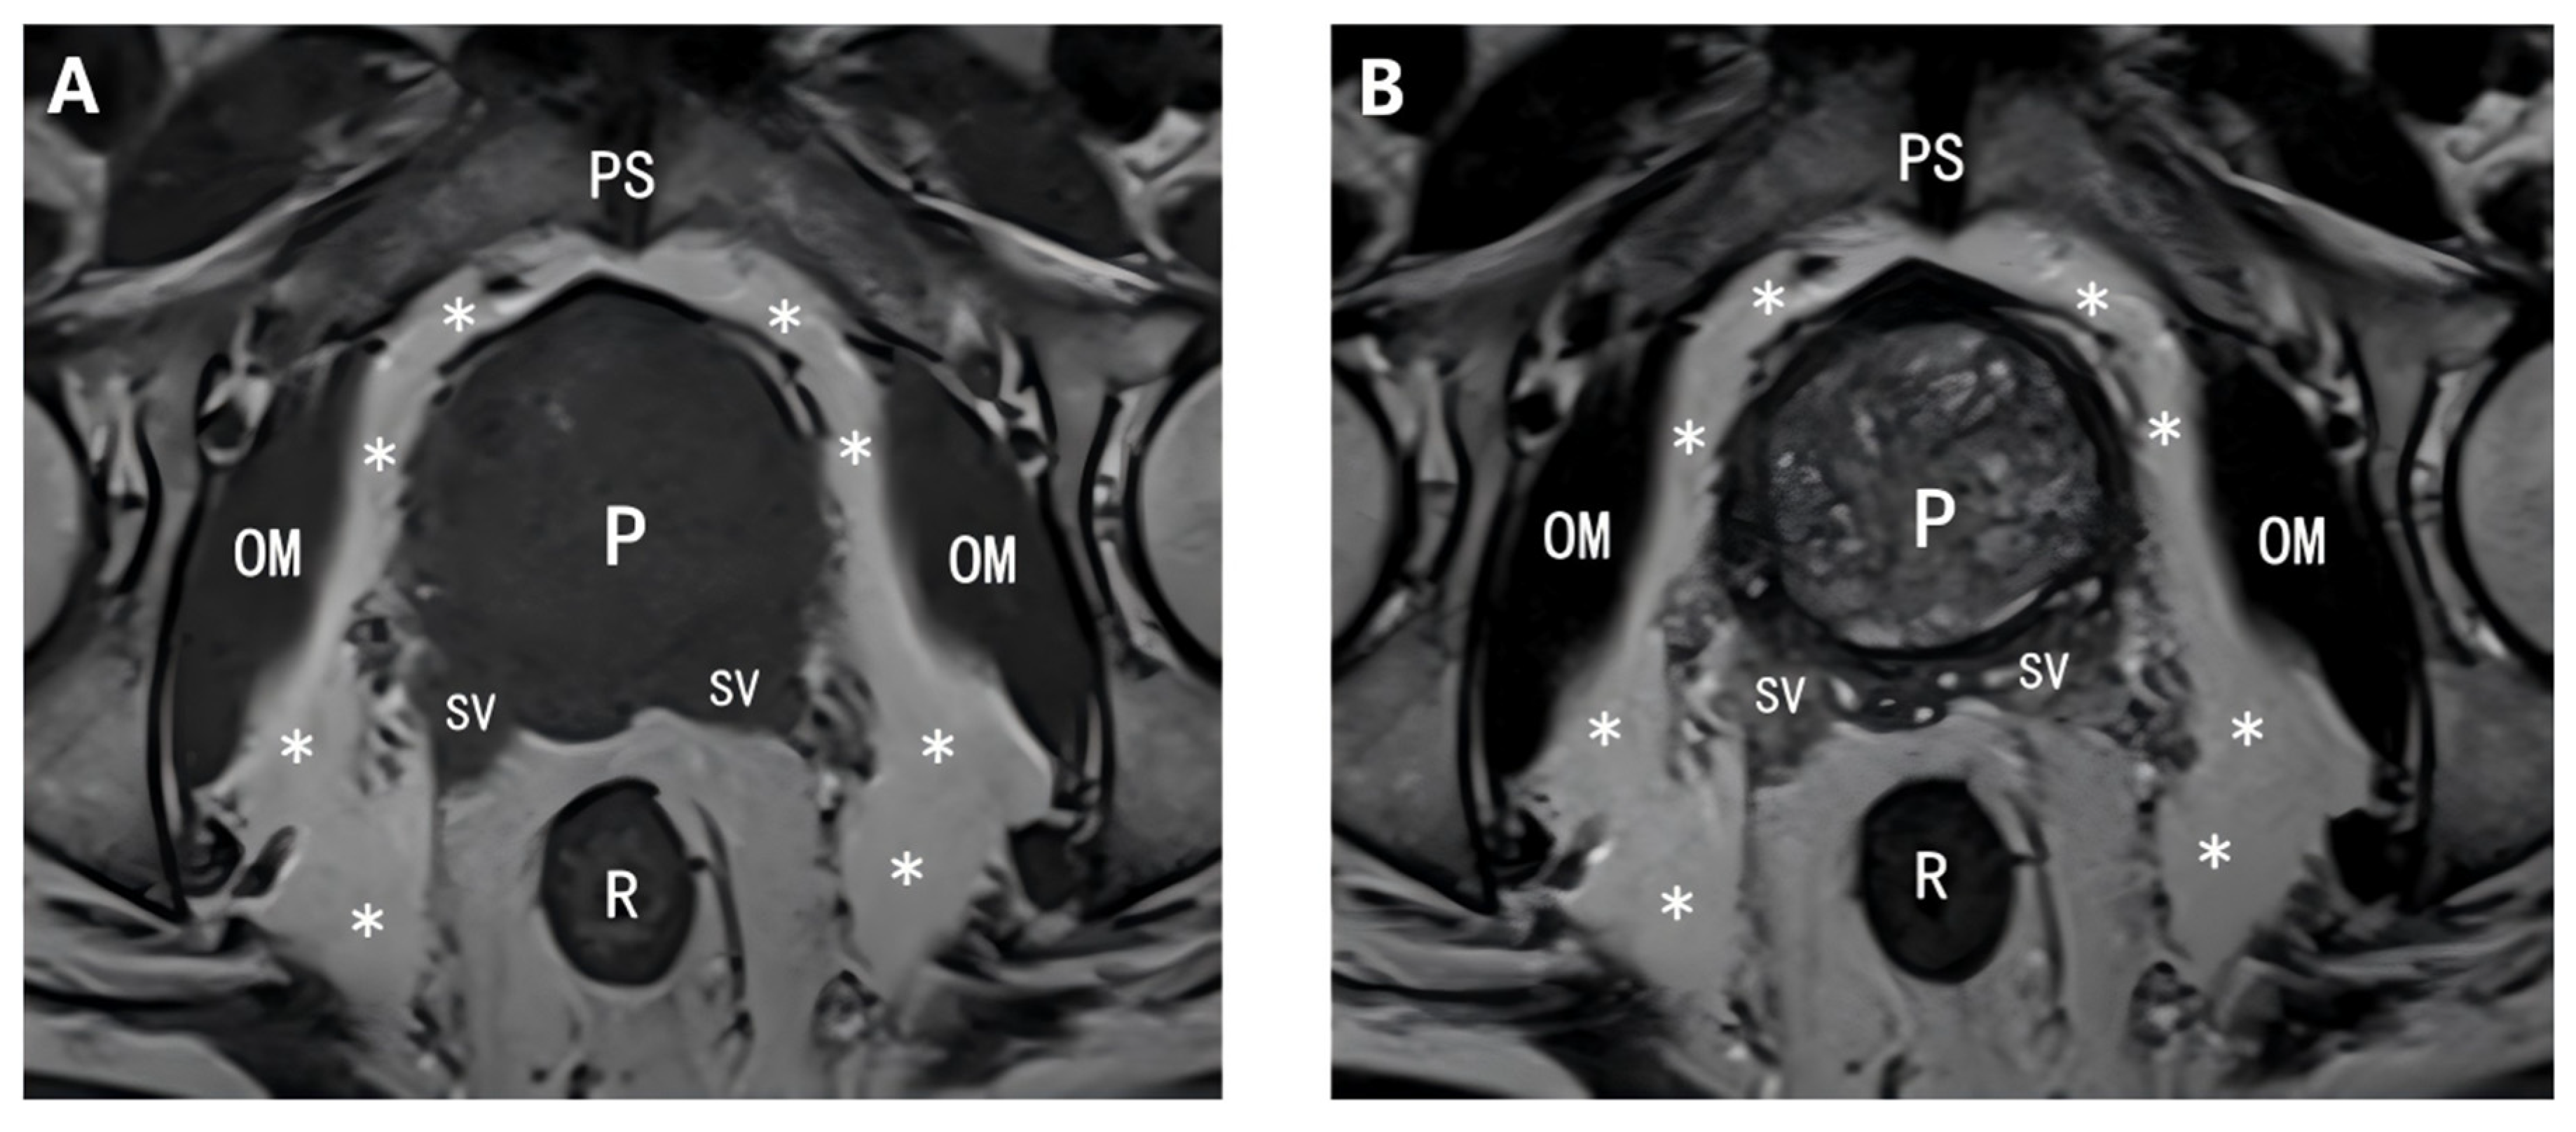

2.4.2. Delineation of PPAT Boundaries and Regions of Interest (ROIs) with Volume Calculation

2.4.3. Segmentation Consistency Validation